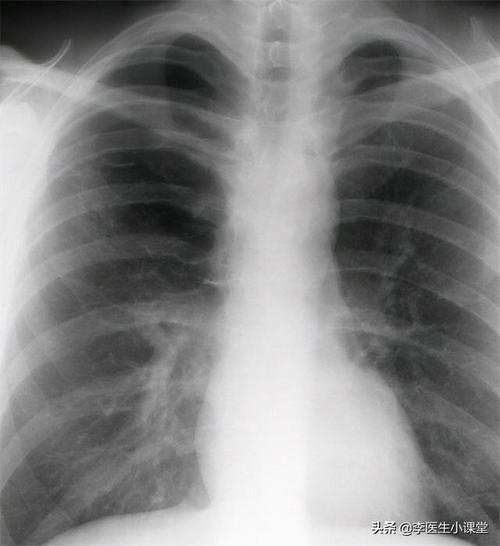

抽烟人肺部x光片图片,抽烟的肺部x光片图片

常吸烟得人身体若有3处疼,肺部8成"百孔千疮",最好戒烟

不吸烟吸烟感染冠状病毒三个肺部x光照片看完我想戒烟了

抽烟的肺部x光片图片

正常肺部x光片图片

正常人肺部x光片

肺部x光片正常图

正常肺部x光片

肺部x光片

肺部x光片怎么看

肺部x光片阴影

肺癌x光片

肺结核x光片

肺癌早期x光片